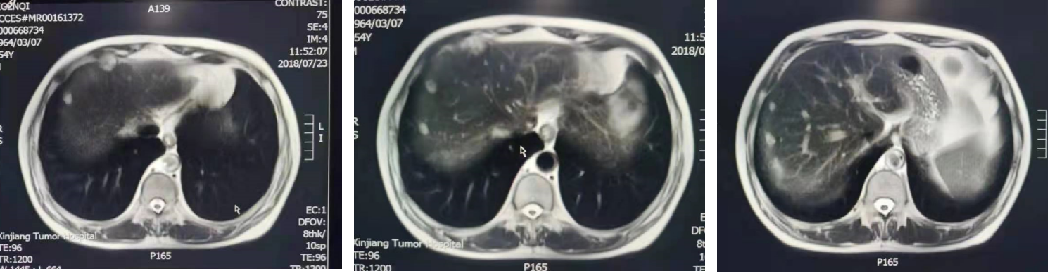

2020-03至2020-05月 5周期伊立替康+卡培他滨+贝伐珠单抗。

2020-04 复查CT:腹膜病变较前缩小。

2020-06 复查CT:腹盆腔少量积液,腹膜增厚,较前变化不大。因患者乏力及消化道反应,2020-06至2020-09 贝伐珠单抗+卡培他滨片。

2020-09 患者因自觉右上腹隐痛,复查CT提示肝脏边缘多发结节部分较前增大;腹膜增厚,较前新发。

肝脏边缘多发结节,部分较前增大,考虑腹膜转移瘤。

腹膜增厚,提示腹膜转移,较前新发。